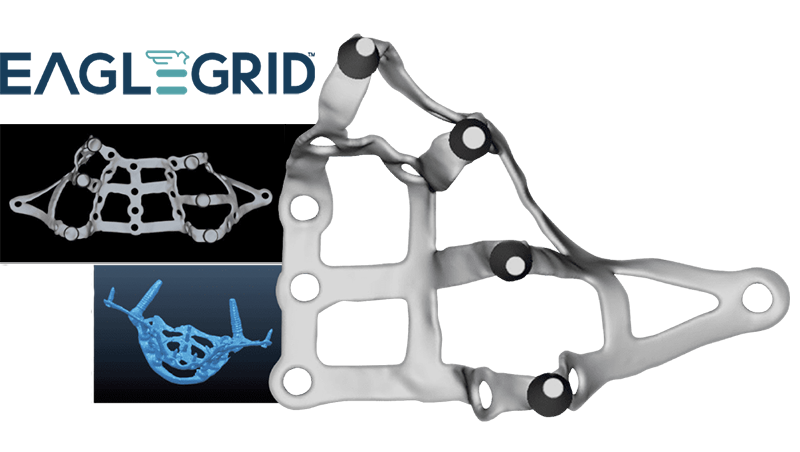

Poco osso? Scegli Eagle Grid

Eagle Grid è un nuovo tipo di implantologia che si rivolge ai pazienti che non hanno osso sufficiente per l'implantologia ossea tradizionale.

Un nuovo protocollo impiantare

Eagle Grid è costituito da una struttura metallica (griglia) in titanio, personalizzata per ciascun paziente che si appoggia all'osso mascellare o mandibolare e viene fissata con viti da sintesi.

Il titanio: rappresenta ormai da anni il metallo per eccellenza in implantologia, per le caratteristiche di biocompatibilità con l'osso e per la pressoché assenza di fenomeni di allergia. La griglia è personalizzata: è cioè costruita avendo come stampo l'osso residuo in bocca al paziente. La progettazione e la produzione è gestita da uno staff composto da ingegneri biomedici, medici specialistici, odontotecnici ed esperti informatici, per raggiungere il massimo della precisione con professionalità in ogni fase di lavorazione.

L'Eagle Grid può risolvere casi di totale mancanza dentale mascellare mandibolare o ripristinare i denti in isolati settori della bocca che ne sono privi. Una volta appoggiata intimamente all'osso viene fissata con viti in titanio che nel tempo si osteointegreranno alla stregua di piccoli minimpianti. Eagle Grid non necessita di osteointegrazione in quanto la sua ritenzione è meccanica, consente infatti il carico immediato: cioè la possibilità di utilizzare subito una protesi provvisoria cementata direttamente sui monconi della griglia.